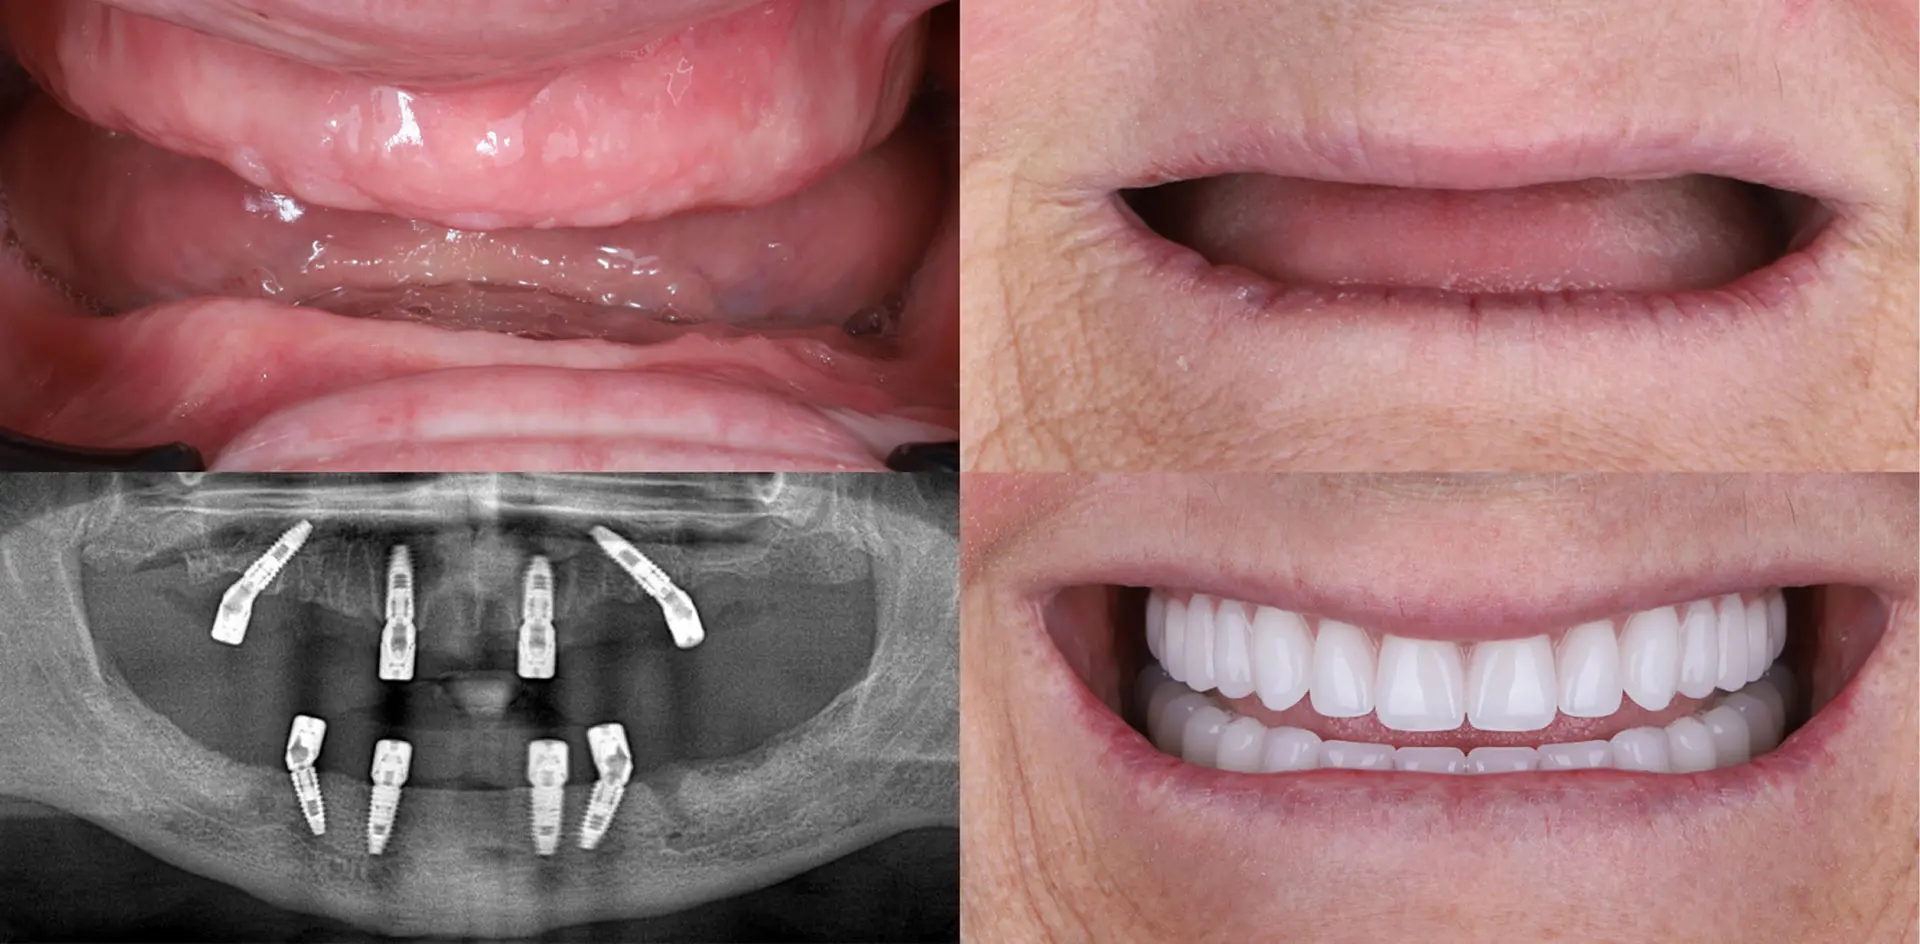

The All-on-4 and All-on-6 methods represent the peak of comfort and innovation in modern dentistry, and the most reliable solution for patients who have lost all their teeth.

By placing four, six, or more dental implants, we create a new, stable foundation for your future smile: a fixed prosthetic restoration that you don’t have to remove.